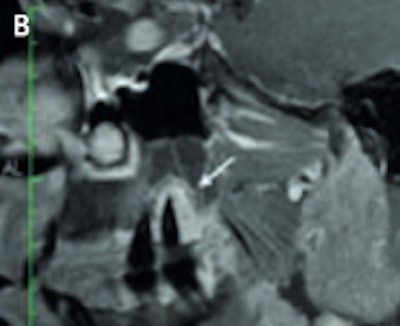

An example of cone-beam CT. In this instance, the lower left third molar (d. 38) was imaged after panoramic radiograph with CBCT. The arrows mark the mandibular canal. Images courtesy of Dr. Anni Suomalainen.